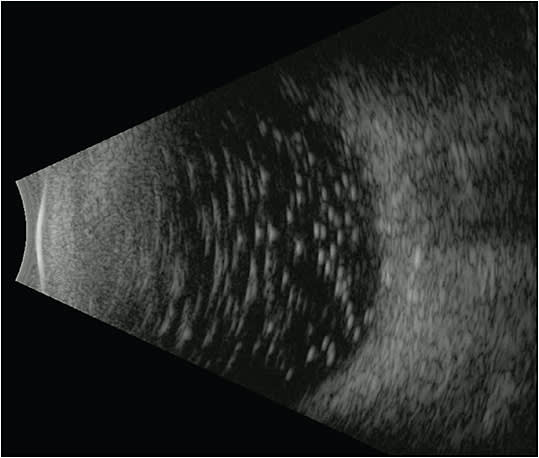

SILICONE OIL INVADING OCULAR TISSUES: RETINA AND OPTIC NERVE

There are few reports of intraretinal SO seen on OCT following SO removal. The mechanism is not entirely well understood, but it may be related to elevated IOP. One study found SO droplets in the retina of a patient after macular hole repair with ILM peeling. The authors postulated that defects in the ILM provided an entryway for the emulsified oil.26

Another report of a patient who underwent multiple RD repairs with otherwise unexplained visual loss and patchy central visual field deficits described numerous small echogenic particles in the vitreous cavity and a hyper-reflective structure within the optic nerve head.27 Swept-source OCT revealed multiple hyper-reflective spaces within the prelaminar optic nerve head, and adaptive optics imaging confirmed that these were similar size and shape to the oil droplets in the vitreous cavity.27 The authors concluded that oil droplets migrating into the retina and optic nerve head may be associated with the progressive visual loss. Similarly, Shields and Eagle described a case of SO infiltration in the entire length of the optic nerve in a patient who underwent RD repair following trauma.28 Their report contains histopathologic images of numerous silicone vacuoles within the optic nerve.